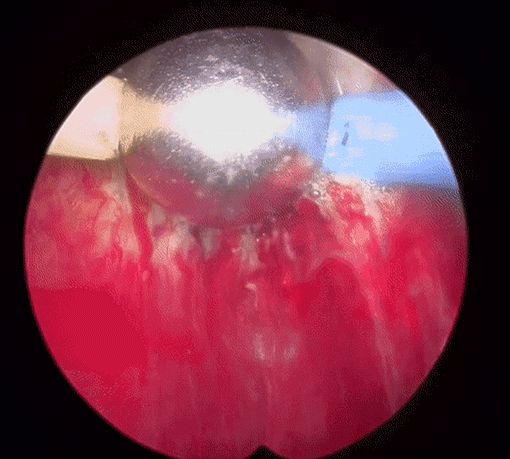

플라즈마 기화술(TURis Plasma Vaporization)은 70°C 이하의 낮은 온도에서 플라즈마를 발생시켜 비대해진 전립선 조직을 기화시키는 매우 안전하면서도 확실한 치료효과를 기대할 수 있는 혁신적인 시술 기법입니다.

70°C 이하의 낮은 온도로 조직이 기화되기 때문에 기존의 레이저 수술과 달리 고열로 인한 주변 조직 손상이 없습니다. 직접 접촉 없이 비대된 전립선 조직을 정확하고 신속하게 제거할 수 있으며 시술시간과 회복기간도 짧고 통증이 적다는 장점이 있습니다. 또한 출혈이 거의 없고, 조직 기화에서 오는 부작용도 미미할 만큼 낮습니다.

플라즈마를 활성화 상태로 후방으로 이동하고, 비활성화 상태로 전방으로 이동하며 조직을 제거 합니다.